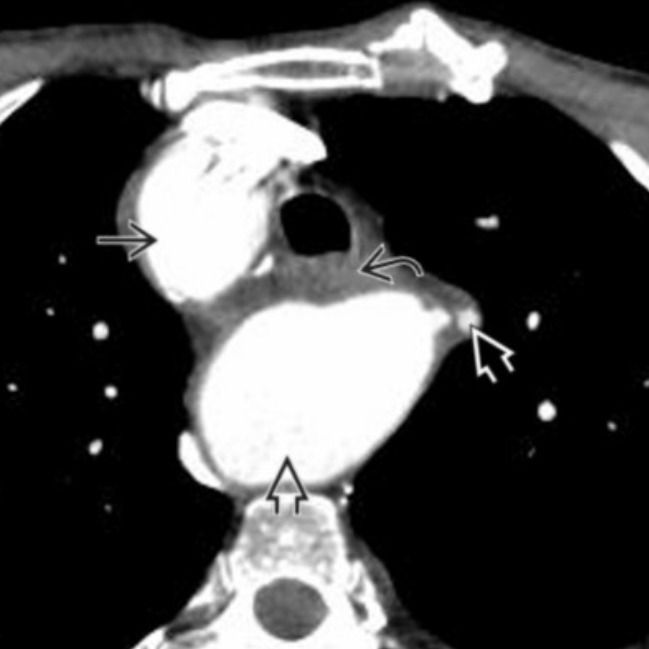

What is the anomaly

Right aortic arch (pushing trachea to the L)

With large posterior diverticulum of Kommerell (post to trachea and esophagus)

Diverticulum gives rise to stenotic L subclavian artery